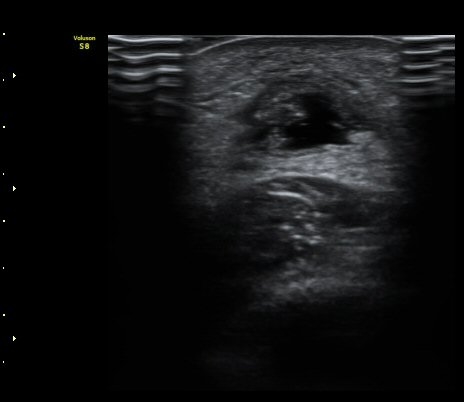

[¹ß¸ñ] ¾ÆÅ³·¹½º ÈûÁÙ ÆÄ¿­ÀÇ ÃÊÀ½ÆÄ Áø´Ü

ÁÂÃø ¹ß¸ñÀÇ ÅëÁõ(2ÁÖ)

2ÁÖ Àü ¹èµå¹ÎÅÏÇÏ´Ù°¡ ¹ß¸ñÀÇ ÅëÁõÀÌ ¹ß»ýÇÏ¿© Ÿº´¿ø¿¡¼­ ÃÊÀ½ÆÄ°Ë»ç µî ½ÃÇàÇÏ°í ºÎ¸ñ°íÁ¤ ÈÄ ¹°¸®Ä¡·á À§ÇØ ³»¿ø

¾ÆÅ³·¹½º°Ç ºÎÁ¾ ¹× ¾ÐÅë, ´Éµ¿Àû ¹ß¸ñ ¹ß¹Ù´ÚÃø ±¼°ñ G 1, thomson test(+).

ÃÊÀ½ÆÄ °Ë»ç